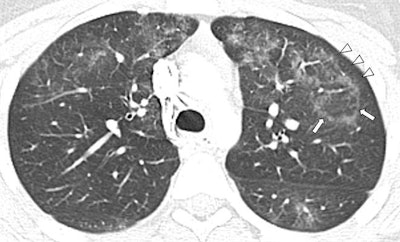

On the CT scans, ground-glass opacity was evident in all of the patients, consolidation in 64%, and interlobular septal thickening in 14%, with subpleural sparing in 79% of the cases. The extent of abnormality visible on CT exceeded 75% of the lungs in the vast majority of cases. About 36% of the patients' CT scans also showed the reversed halo sign.

For both imaging modalities, the abnormalities were bilateral for all cases and were symmetric in all but one. Half of the x-rays and CT scans showed lower lobe predominance. Interobserver agreement was nearly perfect between the two pediatric radiologists who examined the chest x-rays and CT scans.